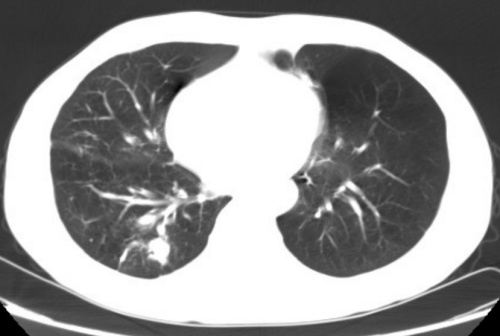

据了解,王先生长期吸烟,有多年的慢性支气管炎、肺气肿,11月24日因CT体检发现右下肺结节,于12月1住进普胸外科、心脏大血管外科。普胸外科、心脏大血管外科副主任医师罗化接诊了他。经过PET-CT检查,王先生患肺癌可能大,无远处及淋巴结转移,需手术治疗。但考虑王先生年龄大,又长期吸烟,有慢性阻塞性肺部疾病,肺功能差,难以耐受肺全麻胸腔镜手术。科室副主任、主任医师杨继承查看患者后立即组织团队研究讨论,决定采取肺部微波消融治疗。为了缓解王先生的紧张情绪,杨继承告知王先生:“目前针对肺结节、肺癌有很多方法,除了常规胸腔镜手术外,还可以进行局部消融术,就是在CT引导下经皮肺插一根针到肺部结节中,几分钟结节就消失,不需要全麻,恢复快,创伤小”。王先生听后打消了疑虑,欣然接受。

12月4日,杨继承带领手术团队在CT引导下给王先生进行了肺部结节微波消融手术。选取合适体位、CT确认进针方向后,首先局麻下进行结节穿刺活检,快速病理确认为肺鳞癌,确定为患者微波消融。杨继承考虑结节离胸膜近,消融过程中微波针热刺激胸膜会造成患者疼痛,于是给予患者人工气胸,使肺结节远离壁层胸膜,然后在CT引导下插入15cm长的微波消融针进入肺部结节进行消融。5分钟后结节消失,手术顺利,患者未感不适,于12月7日顺利出院。

术后三天结节部位坏死、炎性水肿改变